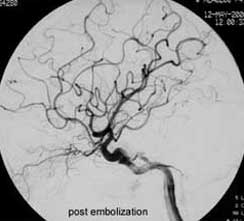

二、脑动静脉畸形(AVM)

---- Spetzler对AVM的分级方法已越来越多地被人们接纳和采用。脑AVM最危险的症状之一是出血。AVM每年的出血率为 3%~4%,第一年内再出血约6%。每次出血的致残率为30%,病死率为12.5%,而积极治疗的总残废率加病死率在10%以下。

---- 血管内栓塞对于单支或少数供血动脉的AVM,特别是新近出血的病例,可以达到微侵袭、痛苦小、疗效迅速的目的。 近来改变栓塞方式,将导管直接放置 畸形血管团内,注射NBCA胶,可使畸形团的解剖 治愈率提高至27%。再加上更细、超 滑的微导管问世,栓塞的并发症更为降低。针对大型、功能区 的AVM栓 塞可缩小其体积,改善血液动力学分布,以利于显 微外科技术切除或放射外科治疗,是后二者的重要辅助手段。

----立体定向放疗(γ-刀、χ-刀)对AVM是一种有希望的选择性治疗方法。据文献报道,AVM治疗后年消失率30%~50%,2年 消失率70%~90%,其消失速度与所用的照射量成正比,与AVM 的大小成反比。从治疗到AVM完全闭合之前每年的出血率 3%~4%,与自然出血史相同,所以对有出血史的患者,应优先采用栓塞或手术方法。大型AVM经若干次栓塞后体积缩小即可 放射治疗。但栓塞物质应是NBCA。其它颗粒或丝线栓塞,均有复发之虞。栓塞加立体定向放疗可使60%~80%的患者免于开颅 手术而获治愈。